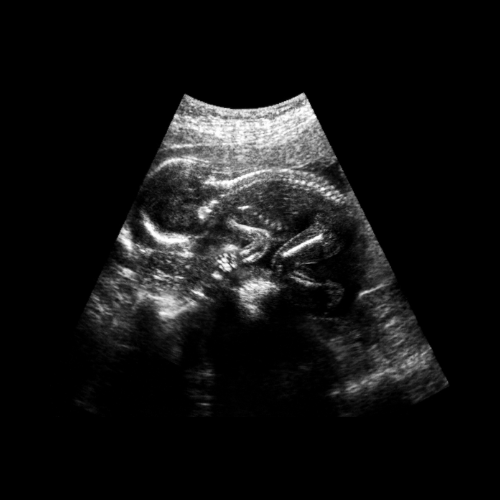

A fetal growth scan is a specialized ultrasound performed between 28 and 32 weeks of pregnancy. This scan measures your baby’s growth, checks organ development, and ensures overall fetal health. It is especially important to detect growth concerns, facilitate timely interventions, and plan for a safer delivery.

What Does the Fetal Growth Scan Involve?

During the scan, these parameters are checked:

- Anatomical Survey: Brain, spine, heart, kidneys, and bladder